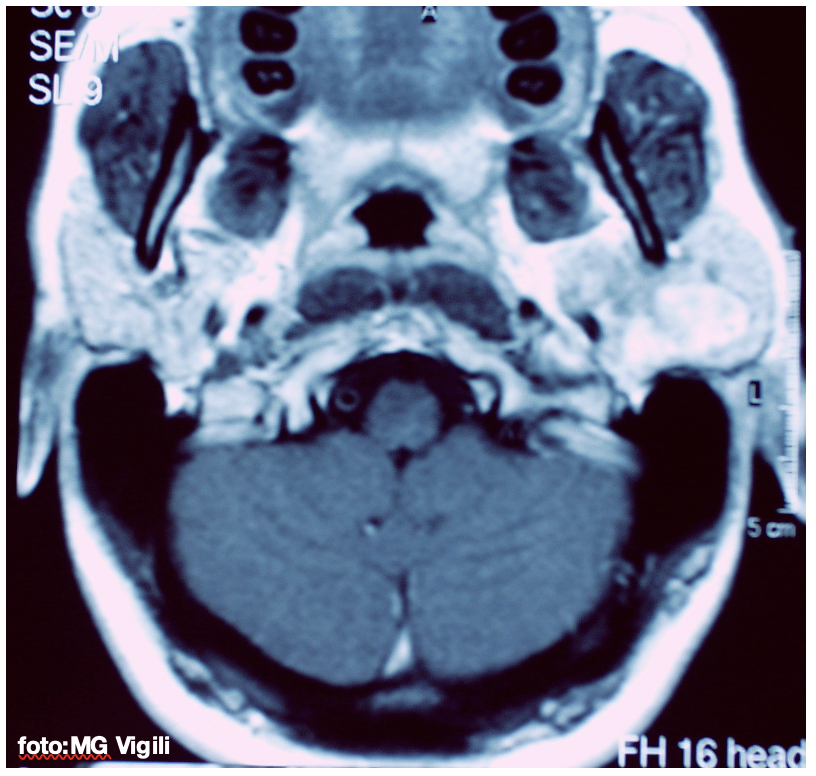

Recidive di Adenoma Pleomorfo e tipo di chirurgia: studio di metanalisi italiano. Uno studio di metanalisi italiano dell’Università La Sapienza di Roma, su 51 studi selezionati per un totale di 2095 pazienti, ha indagato la correlazione fra tipo di chirurgia eseguita e recidiva di Adenoma Pleomorfo (PAs), il più comune fra i tumori delle ghiandole salivari.

Dopo Parotidectomia parziale superficiale (PSP), le recidive scendono a 0.73%. L’Adenoma Pleomorfo recidivo è spesso multifocale (RPA).